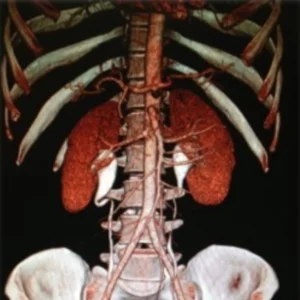

The kidneys are a pair of bean-shaped organs on either side of your spine, below your ribs and behind your belly. Each kidney is about 4 or 5 inches long, roughly the size of a large fist.

The kidneys’ job is to filter your blood. They remove wastes, control the body’s fluid balance, and keep the right levels of electrolytes. All of the blood in your body passes through them several times a day. Blood comes into the kidney, waste gets removed, and salt, water, and minerals are adjusted, if needed. The filtered blood goes back into the body. Waste gets turned into urine, which collects in the kidney’s pelvis — a funnel-shaped structure that drains down a tube called the ureter to the bladder.Each kidney has around a million tiny filters called nephrons. You could have only 10% of your kidneys working, and you may not notice any symptoms or problems. If blood stops flowing into a kidney, part or all of it could die. That can lead to kidney failure.